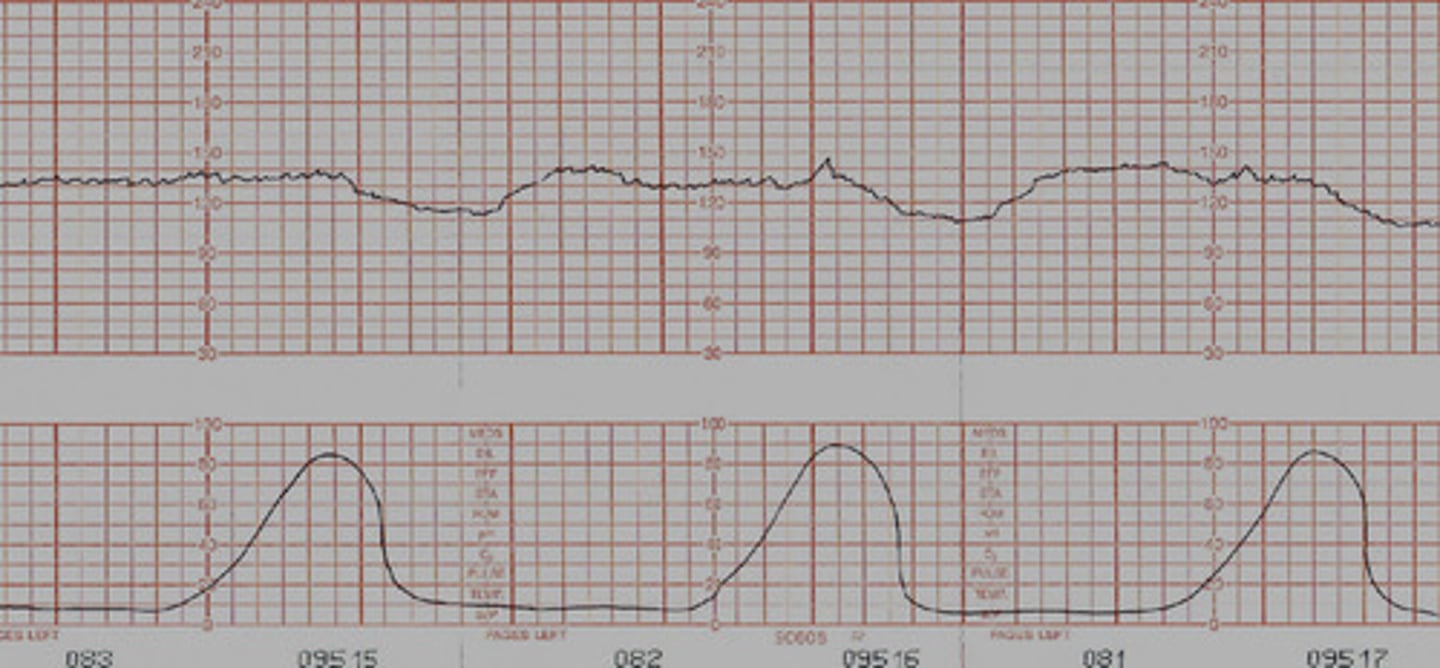

Early Decelerations

- mirrors contraction perfectly

*the FHR baseline begins to dip with the beginning of a contraction, FHR baselineis back to normal by the end of the contraction

- D/t head compression

Nursing interventions for early decelerations

- change position if possible (left is best)

- apply oxygen

- IV bolus (consistent decels)